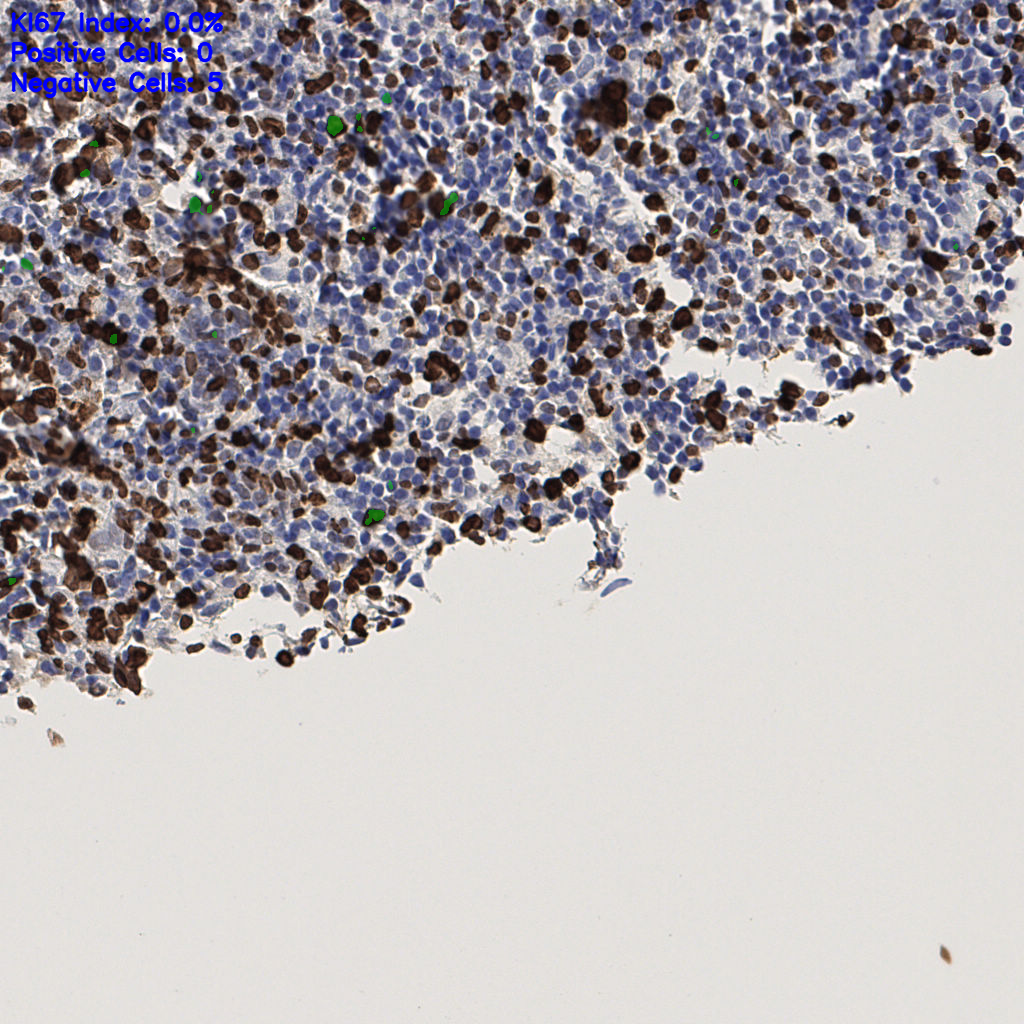

slice_50_10_x44800_y8960.png

slice_50_10_x4480...

slice_50_18_x44800_y16128.png

slice_50_18_x4480...